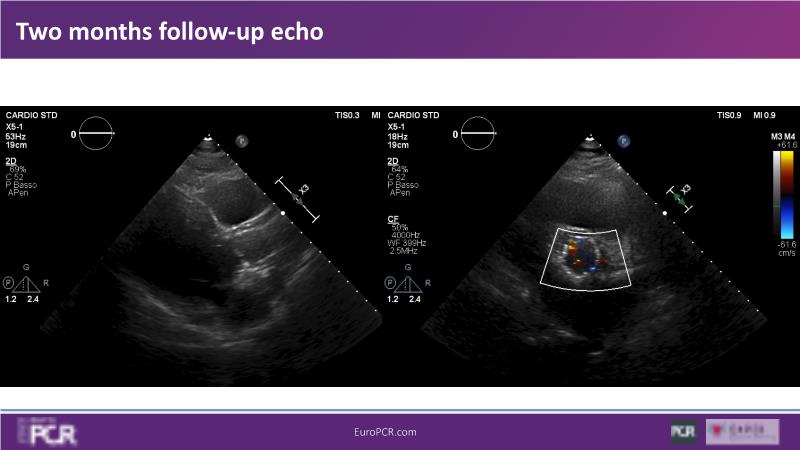

Discover the key factors to consider in selecting the optimal valve and implant technique for transcatheter aortic valve implantation (TAVI) to achieve optimal procedural outcomes. Gain insights into the impact of device choice and implantation technique on coronary access following TAVI and learn valuable strategies for tailoring your TAVI technique to complex scenarios, including bicuspid aortic valves, large and calcified anatomies, and ensuring coronary access.

- To learn how to tailor your TAVI technique to complex situations: bicuspid aortic valves, large, calcified anatomies and coronary access